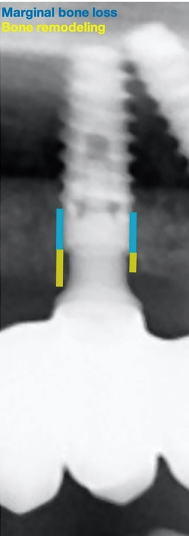

使用CliniView 6.1.3.7软件程序(Instrumentarium, Valencia, Spain)进行影像学测量。以4 mm种植体直径为参考对每次测量进行校准。每个种植体都标明了两种边缘骨水平:一种是向种植体根方计算的边缘骨吸收,另一种向冠方计算的骨改建(图4)。种植体周围边缘骨吸收定义为发生在种植体平台根方的骨水平变化,由此导致种植体的部分粗糙表面不再被骨覆盖。为了计算这个变量,在6个月(T1和T2之间的差值)和12个月(T1和T3之间的差值)之后,通过种植体平台到影像学上第一个骨-种植体接触点来确定每个时间点的骨水平。骨改建被定义为发生在种植体平台冠方的骨水平变化,不会引起种植体粗糙表面的暴露。为了计算该变量,在6个月(T1和T2之间的差值)和12个月(T1和T3之间的差值)之后,通过种植体平台到牙槽嵴边缘的距离来确定每个时间点的骨水平。每个种植体的平均值通过测量近中和远中值来计算。对于角度基台,近中和远中边缘骨水平的变化也是单独测量。所有影像学测量值均由同一位经验丰富的测量者记录。